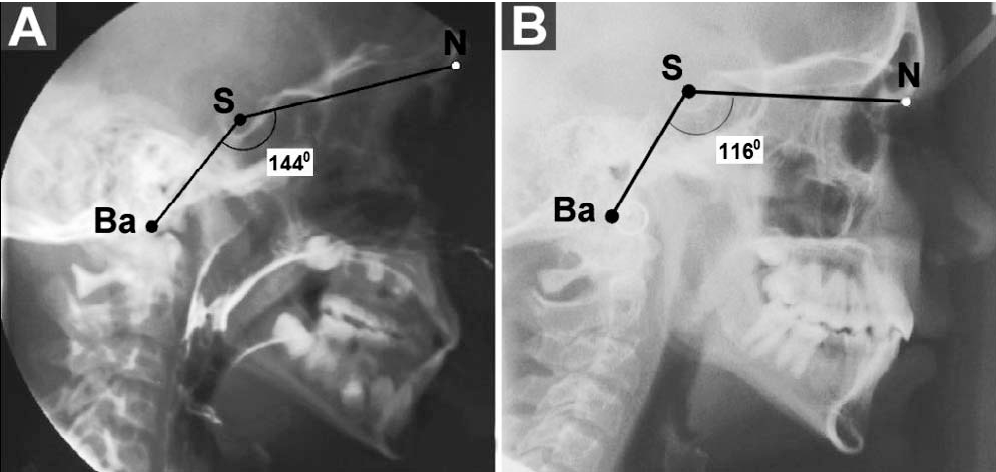

FIGURE 2 Cephalometric radiographs and tracings illustrating Ba-S-N angular variations. Radiographs of a platybasic individual (A) demonstrating an obtuse cranial-base angle (1448) and radiographs of a nonplatybasic patient (B) demonstrating a more acute cranial-base angle (1168). Ba-S-N reference points indicate the cranial-base angle; S-N, anterior cranial base; Ba-S, posterior cranial base. Ba basion; S sella; N nasion.

Radiographs of a platybasic individual (A) demonstrating an obtuse cranial-base angle (1448) and radiographs of a nonplatybasic patient (B) demonstrating a more acute cranial-base angle (1168). Ba-S-N reference points indicate the cranial-base angle; S-N, anterior cranial base; Ba-S, posterior cranial base. Ba basion; S sella; N nasion. Less